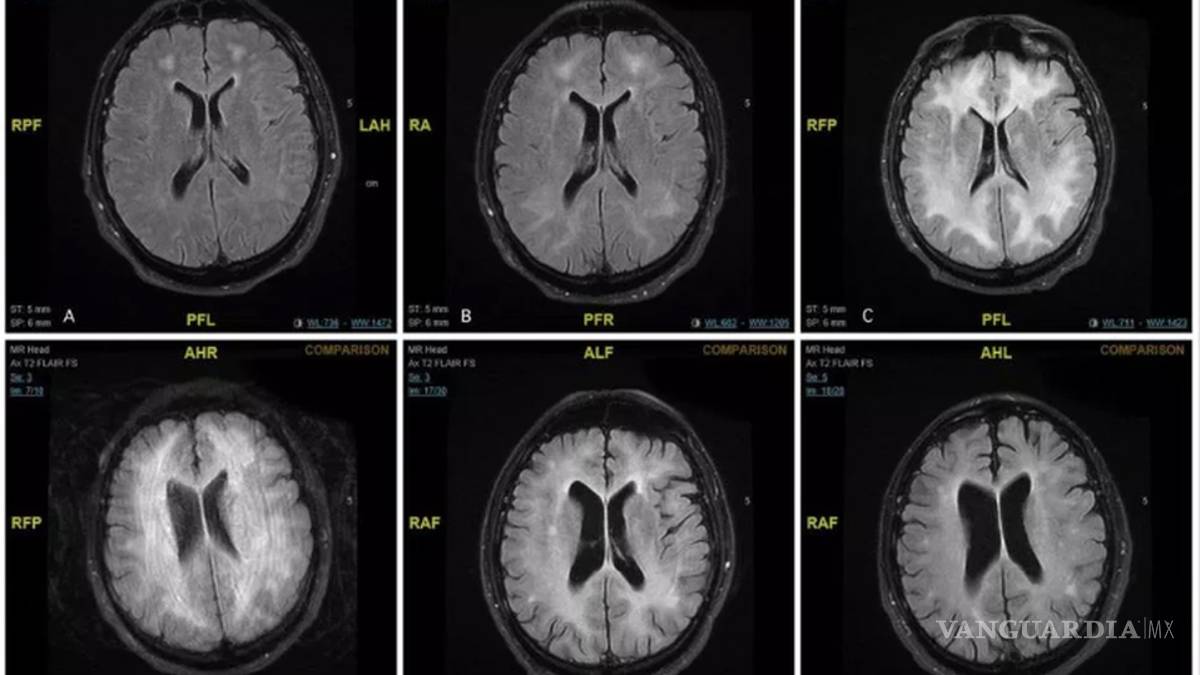

La Leucoencefalopatía es una afección en el cerebro en la que la materia blanca se ve severamente dañada

El diagnostico fue malo: el hombre padecía Leucoencefalopatía, un padecimiento en el cerebro que fue provocado por el consumo de cocaína.

Los médicos realizaron resonancias magnéticas que desmostaron daños severos en la materia blanca del cerebro, se encarga de controlar el aprendizaje, la resolución de problemas, la marcha, el equilibrio y el estado de ánimo.

Abdilla mencionó que la intenció de publicar el informe médico y las resonancias fue crear consciencia sobre las adicciones y el consumo de esta sustancia, que tan sólo en Inglaterra se ha duplicado en los últimos años.